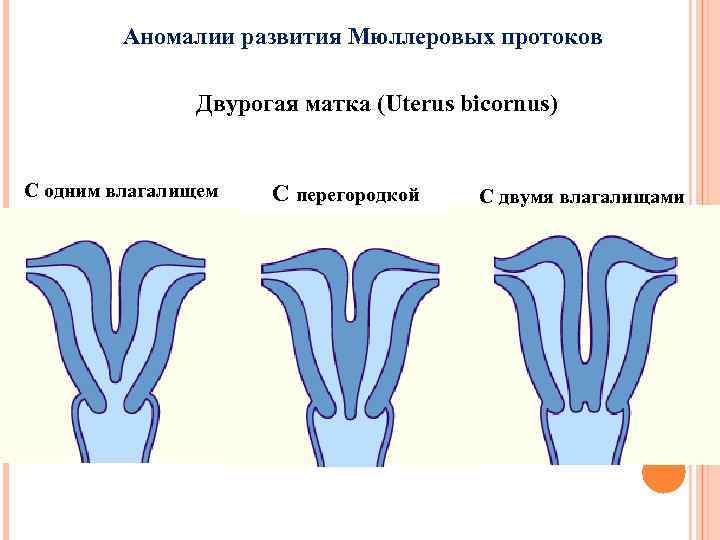

Аномалии развития Мюллеровых протоков Двурогая матка (Uterus bicornus) С одним влагалищем С перегородкой С двумя влагалищами

Аномалии развития Мюллеровых протоков Двурогая матка (Uterus bicornus) С одним влагалищем С перегородкой С двумя влагалищами

Двурогая матка (Uterus bicornus)

Двурогая матка (Uterus bicornus)